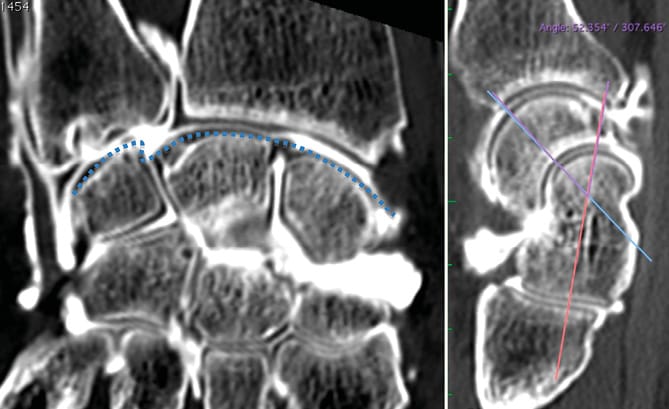

Rééducation Rééducation après fracture du premier métacarpien (Bennett, Rolando) : quel protocole aujourd'hui ?